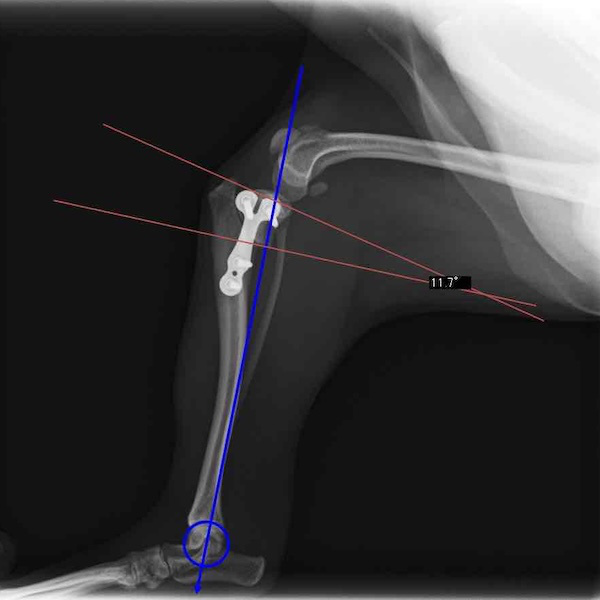

6歳 Mix犬 3.5kg

[主訴]

散歩で駆け出した後にキャンと鳴いてから右後肢を挙上しているとのことで来院。

[検査]

触診検査 MPL左右GradeⅡ

レントゲン検査 にて

右脛骨前方変位あり、ファットパッドサインあり

脛骨公平部角(TPA)の急峻を認める

[治療]

検査結果から前十字靱帯の断裂を疑い脛骨高平部水平化骨切り術(TPLO)を実施することに。また、パテラの安定化のために縫工筋内側広筋切開、滑車溝形成術も併せて実施。

[手術]

前十字靱帯部分断裂

半月板は大きな損傷なし

Fixin T字プレート使用して固定

・術後レントゲン

手術前TPA 28.4° が術後TPA 11.7° に矯正されました。

術後1週間で退院。現在は経過観察中です。

術前TPA計測

手術前

術後TPA計測

手術後

当院ではFixinmicroプレートを使用して小型犬のTPLO手術を実施しております。